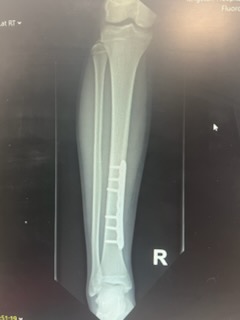

I’m happy to say that the surgery went well. He had a metal plate attached to his tibia with screws, and a new cast below the knee.

The metal plate that has been screwed in to his tibia can be seen here. Weirdly it is quite close to the skin so you can see and feel it on his leg from the outside.

After 9-12 months he will have another operation to remove the metal plate. Then hopefully he will make a total recovery. We are all looking forward to that time.